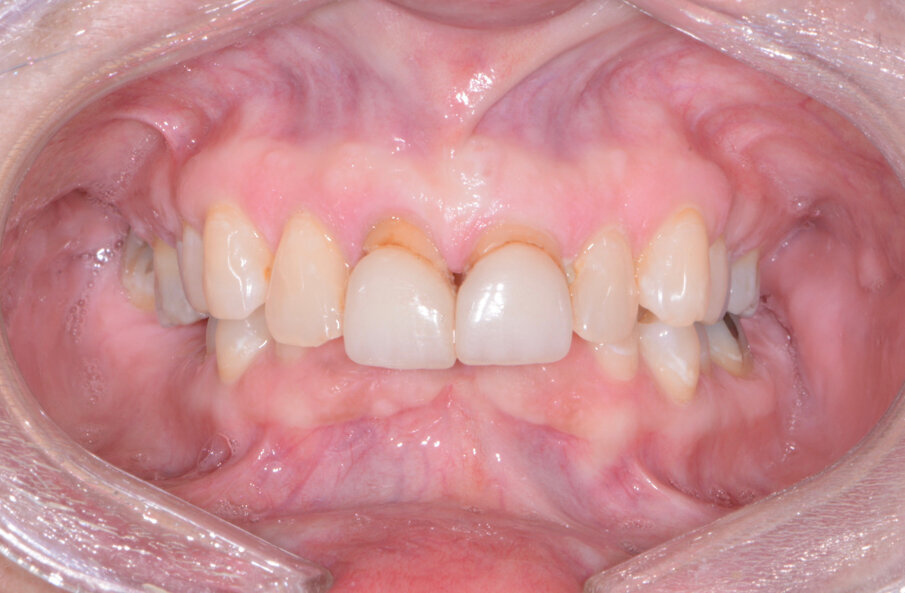

A patient presented to my practice for a consultation wanting to restore her dentition to proper form and function (Fig. 1). She complained of generalised discomfort and mobility in these teeth, apparently due to advanced periodontal disease. There were several teeth in both arches that had Grade III mobility upon clinical examination. Also, there was hyper-eruption in the anterior mandibular dentition due to her jaw position with a deep impinging bite (Fig. 2).

The clinical evaluation included information regarding lip length and support, the position of the natural teeth, occlusion, restorative space and phonetics. In addition, digital images of frontal, side and occlusal views of the dentition as well as facial shots were captured with a Nikon D7200 (PhotoMed).

A few days later, the patient returned for her postoperative appointment with very little discomfort, swelling or bruising. She was very pleased with her new maxillary and mandibular fixed provisional restorations. The occlusion was further checked and adjusted to confirm that there were no interferences in lateral or protrusive movements. The next step in her treatment would consist of full-arch impressions for the definitive restorations approximately four to five months postoperatively.